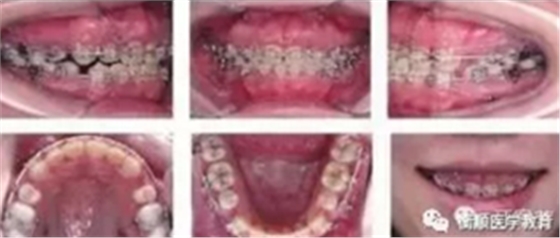

图4 种植体支抗关闭拔牙间隙,同时行上颌前、后牙垂直向控制

本病例在减数4颗第一前磨牙以及4颗智齿后,在治疗中充分应用了微螺钉种植体支抗,双颌后牙区强支抗确保最大程度内收前牙并维持磨牙中性关系;通过利用上后 牙区颊腭侧种植钉持续轻力压低后牙,减小下颌平面角,使下颌逆时针前上旋转,改善侧貌;通过利用上前牙区种植钉轻力压低上前牙,控制前牙覆牙合并改善露龈微笑。保持1年后显示治疗结果稳定,患者对正畸疗效非常满意。